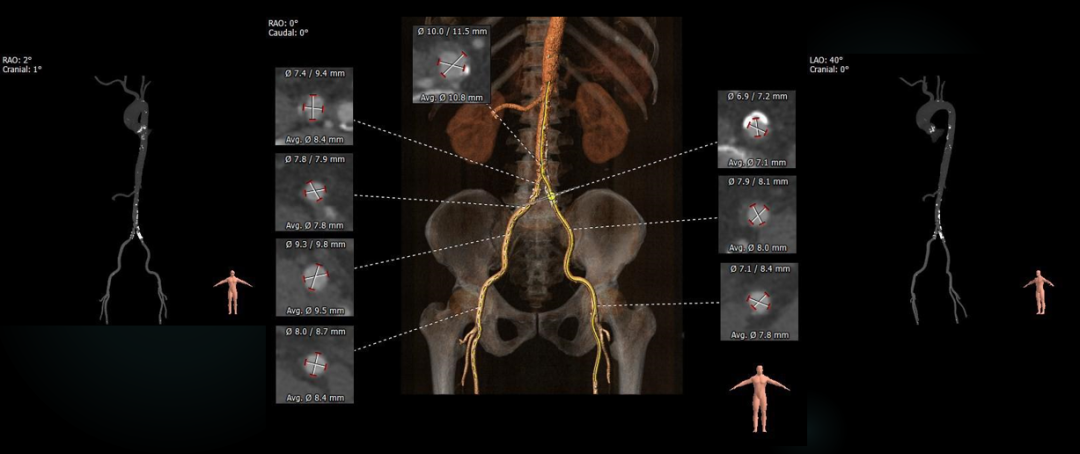

弓部及入路评估

入路血管:外周入路走行可,血管内膜不光滑,降主动脉及双侧髂总动脉分叉处可见多发钙化斑块,血管内径可。